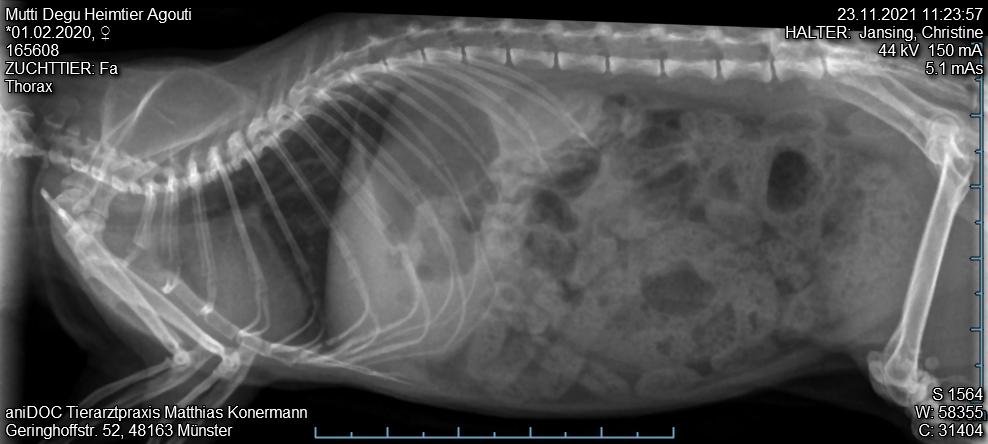

- Mutti_Degu_2021-11-23_11-23-57_Thorax.jpg (58.71 KiB) 3055 mal betrachtet

3. Tierarztbesuch am 23.11. Tier merklich mitgenommen, laute Atmung, nun auch beim Abhören der Lunge. Gewichtsverlust etwa 25-30 g. Sehr schwere Flankenatmung. Röntgenbild unter Gasnarkose. Tierarzt sieht nix drauf, Zähne sind aber gut. Verdacht auf Bauchfellentzündung. Neues AB borgal/riketron 24%, 2 Mal täglich 0.5 ml. Dachte, das Tier überlebt die Nacht nicht. Aber Verbesserung seit dem 25.11. Tier frisst wieder, ist bei 189g.